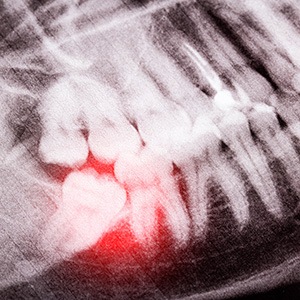

Removing wisdom teeth requires either a simple or surgical procedure. For those molars that have partially erupted and can be seen above the gumline, the use of dental forceps is often enough to move the teeth back and forth until they detach. However, if these teeth are impacted (beneath the gumline), it requires a more invasive procedure.

When a surgical approach is required, our on-staff oral surgeon will make a small incision in the gums after administering local anesthesia. Once the underlying tooth is exposed, it will be sectioned for easier removal. This prevents irritating the bone and makes for a more comfortable and successful procedure.